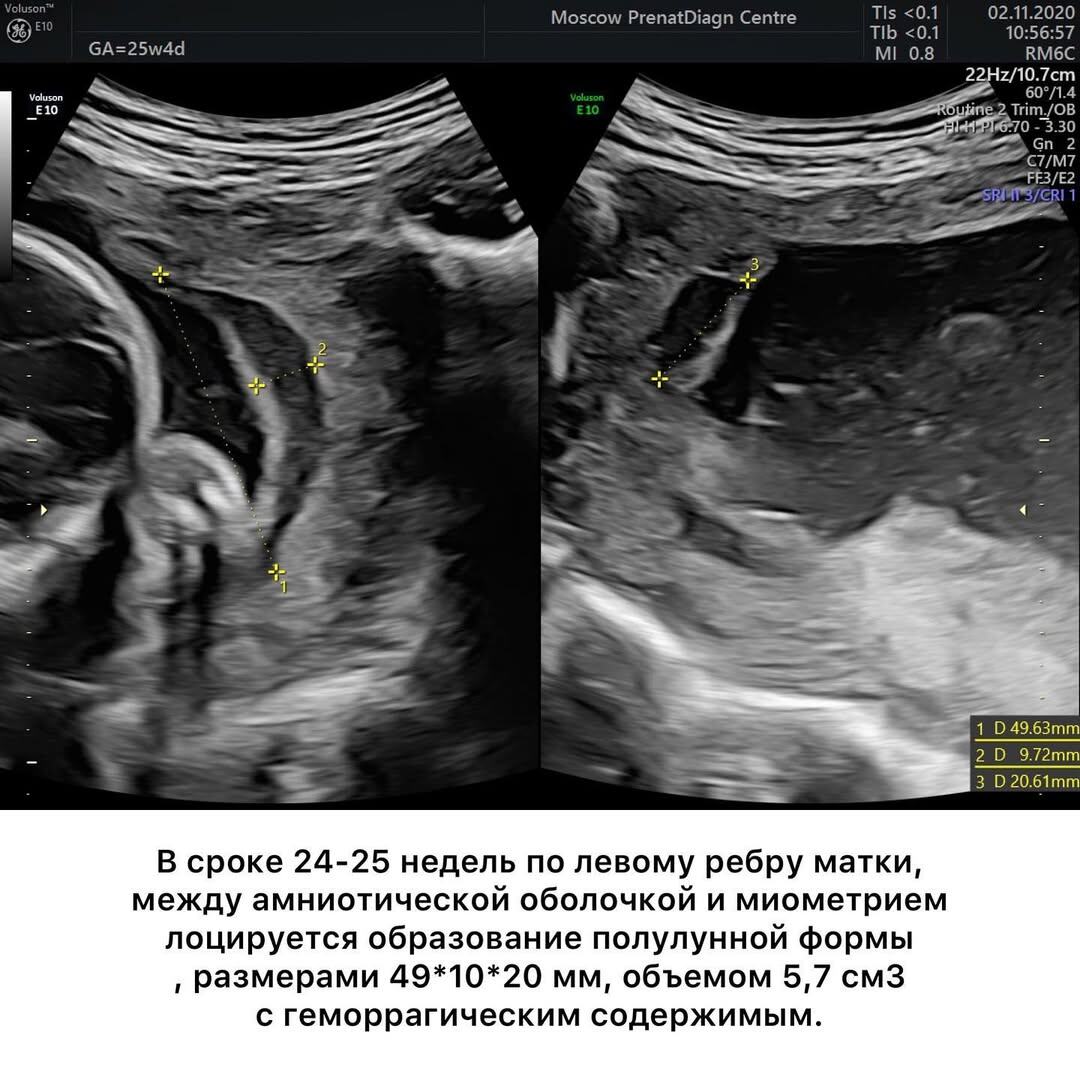

👉Смотрите в галерее, что произошло с ХАС в нашем случае.

Анины кровотечения продолжались до 25 недель. Хорошо, что ей хватило мужества не мчаться каждый раз в стационар на скорой, а ждать, зажав пальцы крестиком. В этой ситуации максимально возможный объем вмешательства — транексамовая кислота. Все остальное, включая постельный режим, не просто не приносит пользы, но даже вредит.